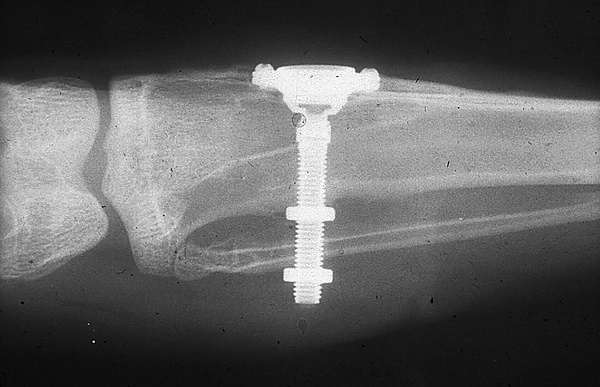

Внутрикостные имплантаты по форме разделяют на корневидные, пластиночные и комбинированные. Наибольшее распространение имеют корневидные имплантаты, которые могут быть цилиндрической или конической формы.

Корневидные имплантаты могут значительно отличаться по макродизайну резьбы: неагрессивная, агрессивная с глубокими полозьями, смешанные.

- с помощью рентгенографии изучаются качество и плотность костной ткани;